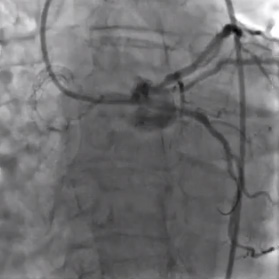

• El angiograma coronario izquierdo mostró ostium separado de las arterias DAI y circunflejas izquierdas.

• La arteria circunfleja izquierda presentaba flujo de TIMI-2. Existía una estenosis subtotal y de elevado grado en la parte proximal.

• Con cierta dificultad, se usó un catéter guía de 6F de soporte adicional para realizar la canulación de la arteria circunfleja izquierda.

• La predilatación fue exitosa con un globo Apex ™ Push de 1.5 x 12 mm; el angiograma posterior demostró la restauración del flujo TIMI-3.

• Una angiografía posterior mostró flujo TIMI-3 sin disecciones, pero aún con una estenosis residual significativa.

• La angiografía final demostró flujo TIMI-3, sin disecciones y sin estenosis residual en el sistema circunflejo izquierdo.